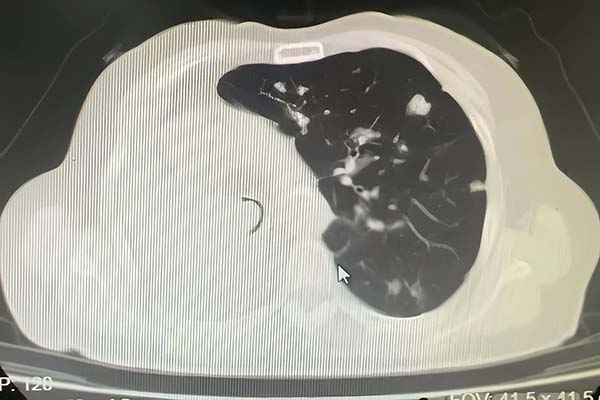

▲患者胸CT提示气管仅留一条缝隙

患者为老年女性,有右肺肿瘤病史1年余,近5个月出现活动后喘息,5天前症状急剧加重,出现呼吸急促、不能平卧等危急情况。患者既往有冠心病、高血压、脑梗、糖尿病等多种基础疾病。外院CT显示其气管下段被肿瘤阻塞,仅存一条缝隙,右肺完全不张,左肺存在多发转移灶,病情十分危重。由外院转诊至垂杨柳医院呼吸与危重症医学科。

患者入院时高枕卧位,呼吸急促,伴三凹征,心率120次/分,血气分析提示伴有II型呼吸衰竭,外院携带CT提示气管下段肿物阻塞,仅留一条缝隙,右肺完全不张,左肺多发转移灶。